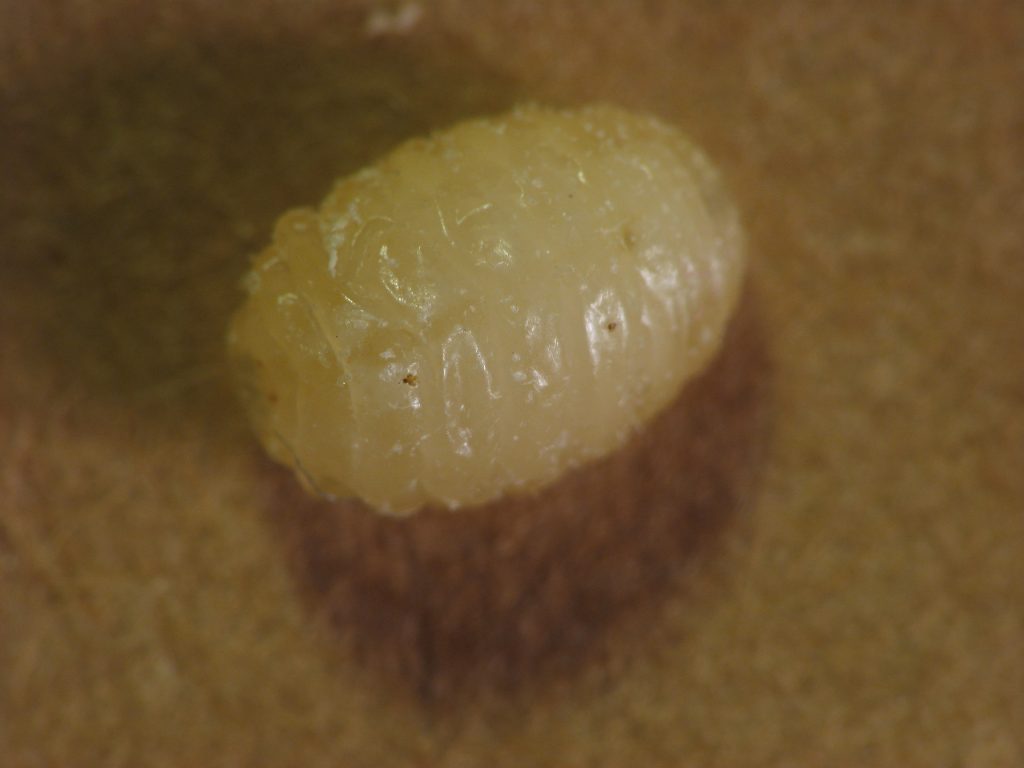

இந்த நிலை, பொதுவாக குடலில் வாழும் நாடாப்புழுவின் லார்வாக்கள் தசை அல்லது மூளை போன்ற திசுக்களில் நுழையும் போது ஏற்படுகிறது. அங்கு அவை தோலின் கீழ் கட்டிகள் போல் உணரக்கூடிய நீர்க்கட்டிகள் போன்ற கடினமான முடிச்சுகளை உருவாக்குகின்றன. இது கேட்க விரும்பத்தகாததாக இருந்தாலும், இவ்வாறாக நுழையும் இந்தப் புழுக்கள் பாதிப்பில்லாதவை மற்றும் இந்த லார்வாக்கள் குறிப்பிட்ட நேரத்திற்கு மேல் உயிர்வாழாது என்று கூறப்படுகிறது.